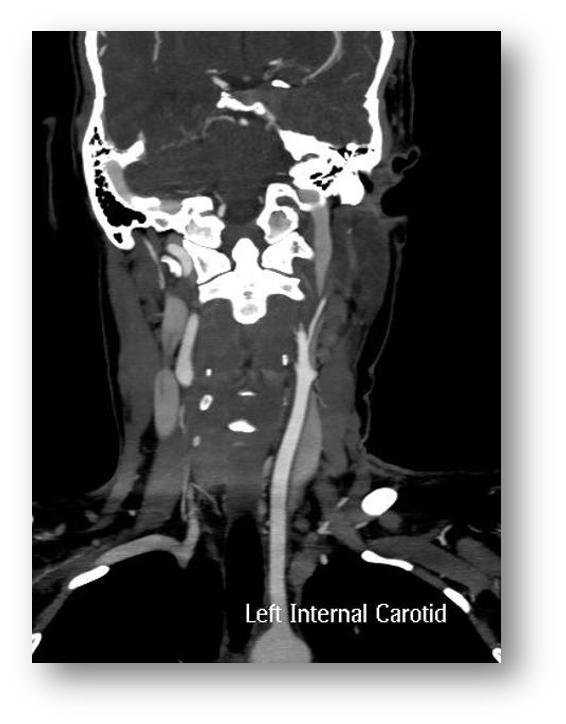

what view is this? what is missing

A

CT angiogram

the interal carotid is not visable because it is occluded